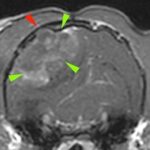

• #2 閉塞性肥大型心筋症ステージB1

循環器科

#2 閉塞性肥大型心筋症ステージB1【循環器科】

<症例情報>雑種猫 2歳7か月齢 去勢済みの男の子 心雑音を認める 主訴:心雑音の精査のた…